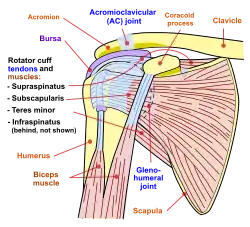

Diagram of the human shoulder joint, front view

Diagram of the human shoulder joint, front view -

The deltoid originates on the lateral third of the clavicle, acromion and the crest of the spine of the scapula. It is inserted on the deltoid tuberosity of the humerus and has several actions including abduction, extension, and circumduction of the shoulder. The supraspinatus also originates on the spine of the scapula. It inserts on the greater tubercle of the humerus, and assists in abduction of the shoulder.

The infraspinatus and teres minor insert on the greater tubercle, and work to laterally, or externally, rotate the humerus. In contrast, the subscapularis muscle inserts onto the lesser tubercle and works to medially, or internally, rotate the humerus.

The four muscles of supraspinatus, infraspinatus, teres minor and subscapularis form a musculo-ligamentous girdle called the rotator cuff. This cuff stabilizes the very mobile but inherently unstable glenohumeral joint. The other muscles are used as counterbalances for the actions of lifting/pulling and pressing/pushing.